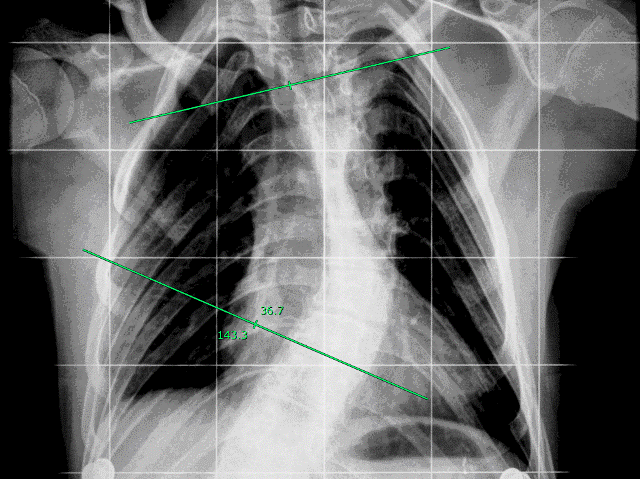

Οι μετρήσεις γωνίας εμφανίζονται σε μοίρες με ακρίβεια +/- 0,5 μοίρες και ακριβώς στην πλησιέστερη μοίρα 0,1. Αυτό χρησιμεύει ιδιαίτερα για ειδικούς της ορθοπεδικής αναφορικά με τη μέτρηση των καμπυλών της σπονδυλικής στήλης.

Εμφανίζονται οι τιμές της εσωτερικής και της εξωτερικής γωνίας σε μοίρες.